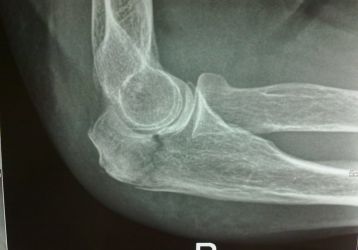

Перелом локтевого сустава: анатомия, симптомы и виды травм локтя

Как определить перелом локтевого сустава: клиническая картина и симптомы. Виды травм: переломы нижних отделов, шейки и головки, проксимального отдела.